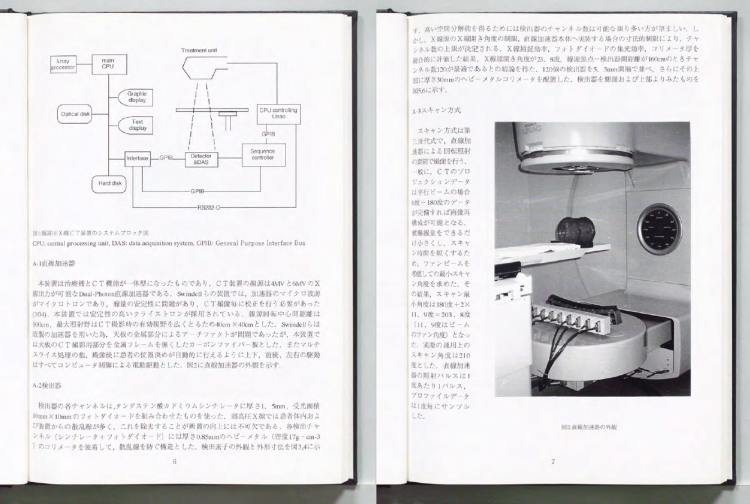

中川:今の大学院生はローカルな話題で学位をとるけど、当時は学位論文といえばもっと壮大な研究をやっていました。私の研究も、機器開発+医学物理+臨床とでもいいましょうか。当時は医学物理士なんて日本にいないですからね。全部自分でやらなくてはいけなかった代わりに、壮大なことができた時代でもありました。

(説明しながら学位論文をみせる)

中川:まずタングステン酸カドミウムクリスタルからフォトダイオードを作って、それを256個並べて 検出器を作るんですね。それで治療器の上でCTをとれる機械を開発しました。マルチリーフコリメーターも開発して。同室CTといって、診断CTと治療CTを同じ部屋に置くわけです。だから今では当たり前にやっているIGRTの技術だけど、私が学位論文でやったのが最初だったというわけです。1990年頃 、正確には学位論文になったのは1989年ですから、そのころの話です。その日のうちに帰ったことなんてなかったですよ。

―――原理的には今のCTと似たようなものですよね、そこから作るなんてすごすぎます。

中川:CTそのものですよ。三菱電機と一緒に開発したんです。